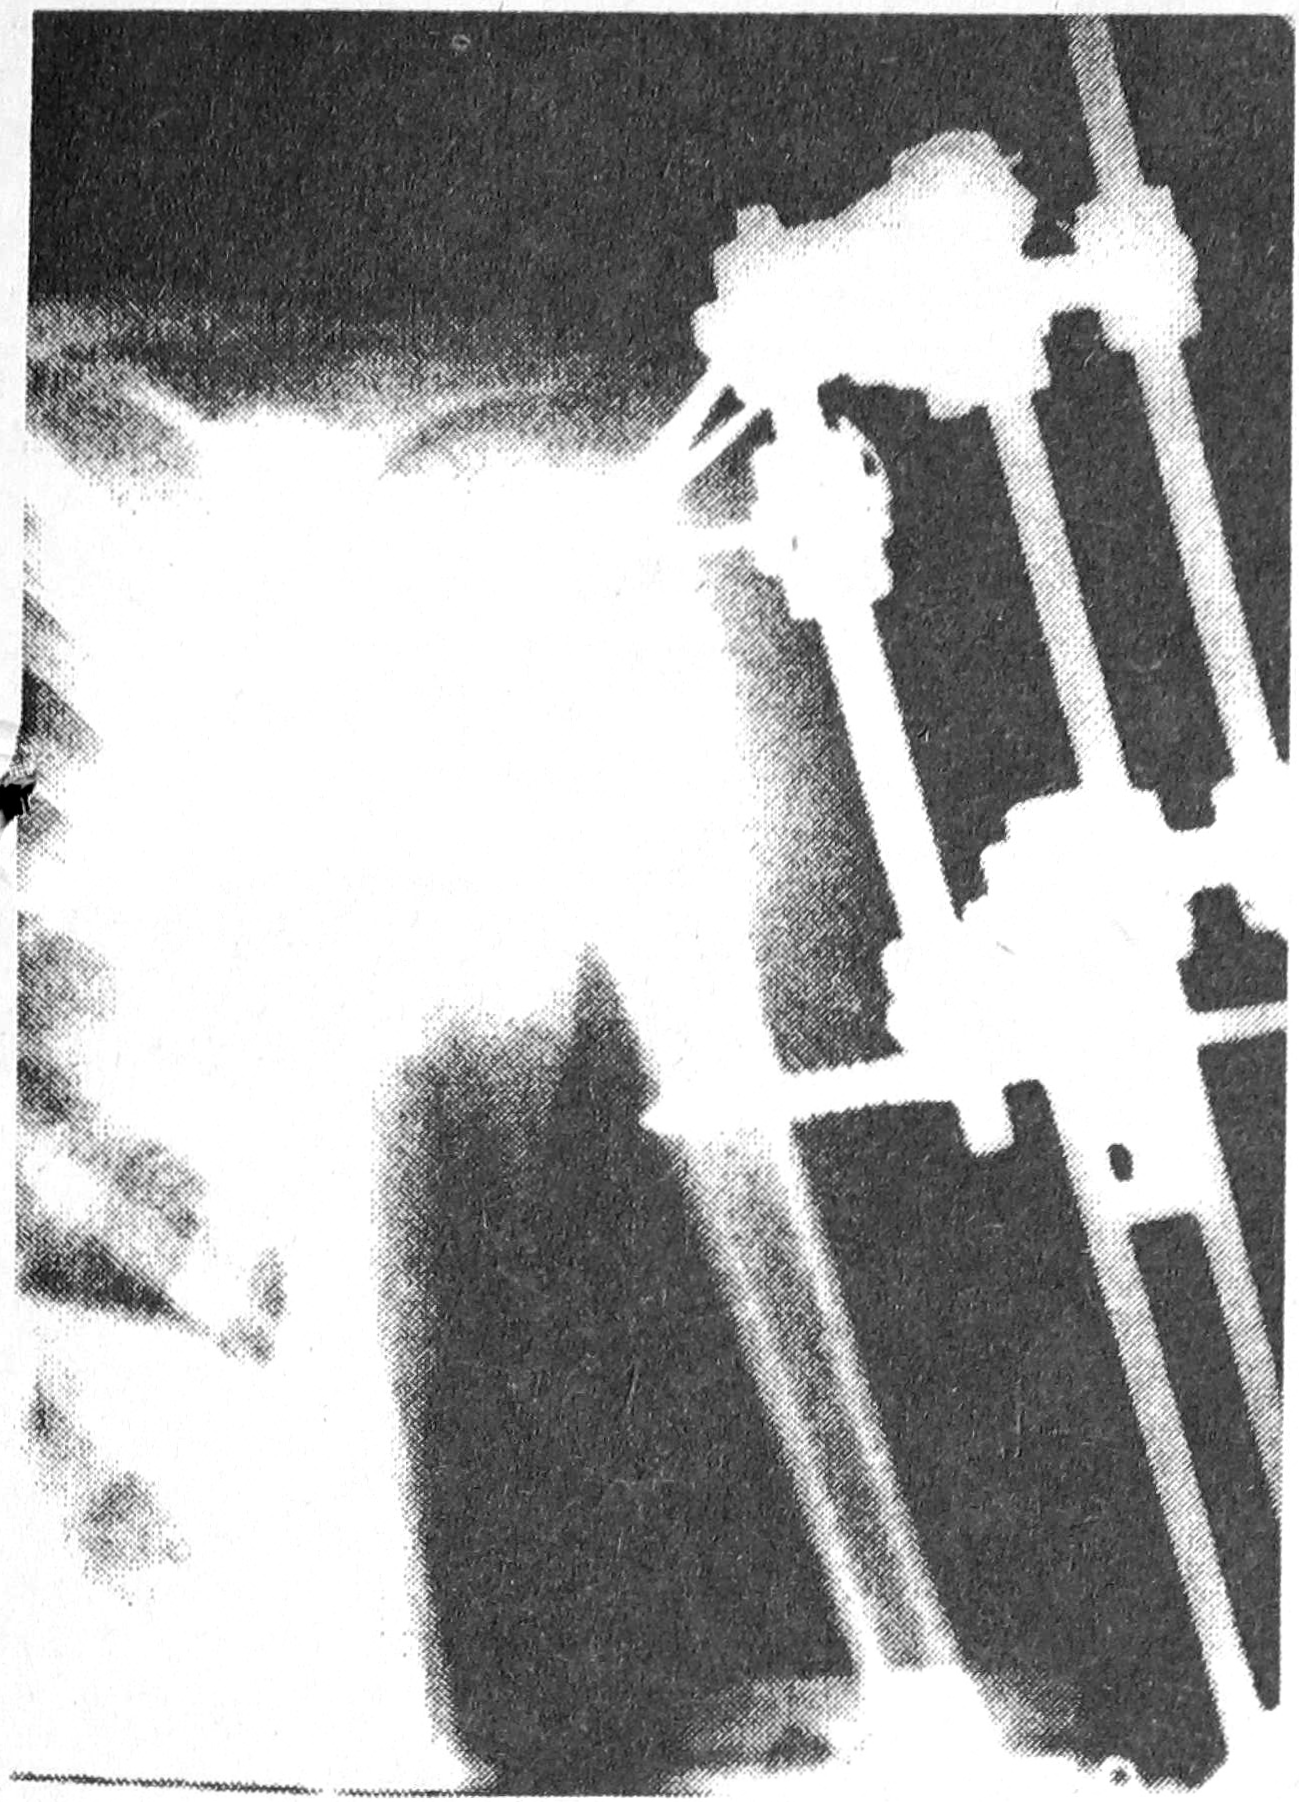

Рис. 2. Рентгенограмма предплечья больной М., 11 лет, с открытым переломом обеих костей предплечья и смещением до операции после остеосинтеза аппаратом внешней фиксации.

Всего в отделении в настоящее время с использованием данного аппарата прооперировано 9 больных (перелом плечевой кости — у 2 детей, перелом костей предплечья — у 5 детей и у 2 взрослых пациентов). У всех больных получены консолидация, отличные и хорошие функциональные результаты. Отдаленные исходы операции пока не изучены. В качестве примера приводим рентгенограммы больных, прооперированных с помощью разработанной конструкции.